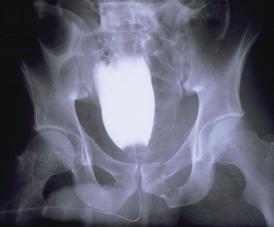

Banda de stabilizare Dallas     Fractura de bazin. Radiografie in

incidenta AP

Fractura de bazin

. Radiografie in incidenta AP   Fractura de spina